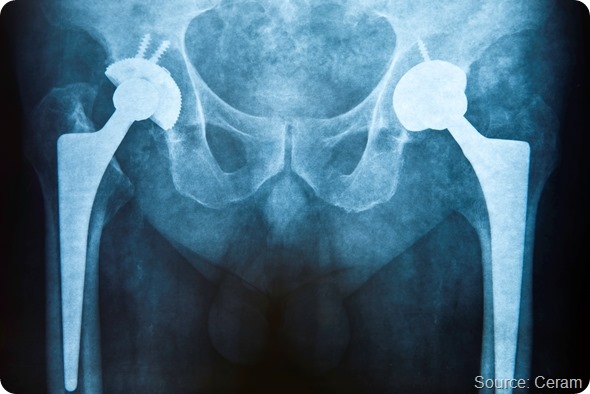

Ceram, the international materials testing and development company, has added biocompatibility testing to the range of services that it offers to the healthcare industries.

Forming part of its regulatory approval testing package, biocompatibility testing is carried out to ISO 10993 and includes extractables/leachables testing, chemical, physical, morphological and topographical materials characterisation and identification/quantification of degradation products.